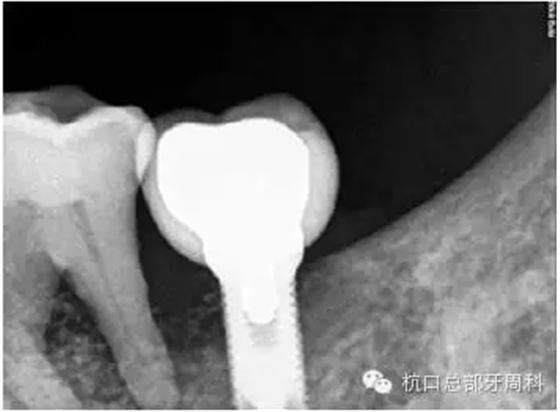

初診時(shí)全景片2011.7

112.webp.jpg

全景片:大范圍火山口樣/彈坑樣骨缺損

CT:左下缺牙區(qū)及部分升支存在骨破壞